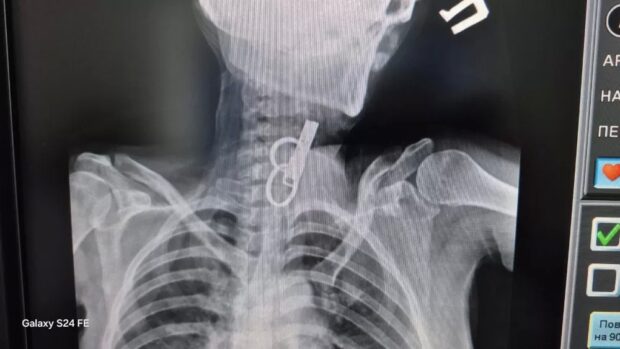

У Гусятинській комунальній лікарні медики провели унікальну маніпуляцію та врятували пацієнта, який випадково проковтнув ключі.

Завдяки майстерності лікарів та наявності сучасного обладнання, велике стороннє тіло вдалося дістати зі стравоходу без жодного розрізу. Операцію виконали малоінвазивним ендоскопічним методом. Саме завдяки їхній злагодженій роботі вдалося уникнути традиційного хірургічного втручання та тривалої реабілітації пацієнта. Про це розповіли у КНП “Гусятинська КЛ” Гусятинської селищної ради.

Наразі чоловік почувається задовільно. Після короткого перебування в реанімації його перевели до загальнохірургічного відділення, де він залишається під наглядом фахівців. Лікарі зазначають, що стан хворого стабільний.